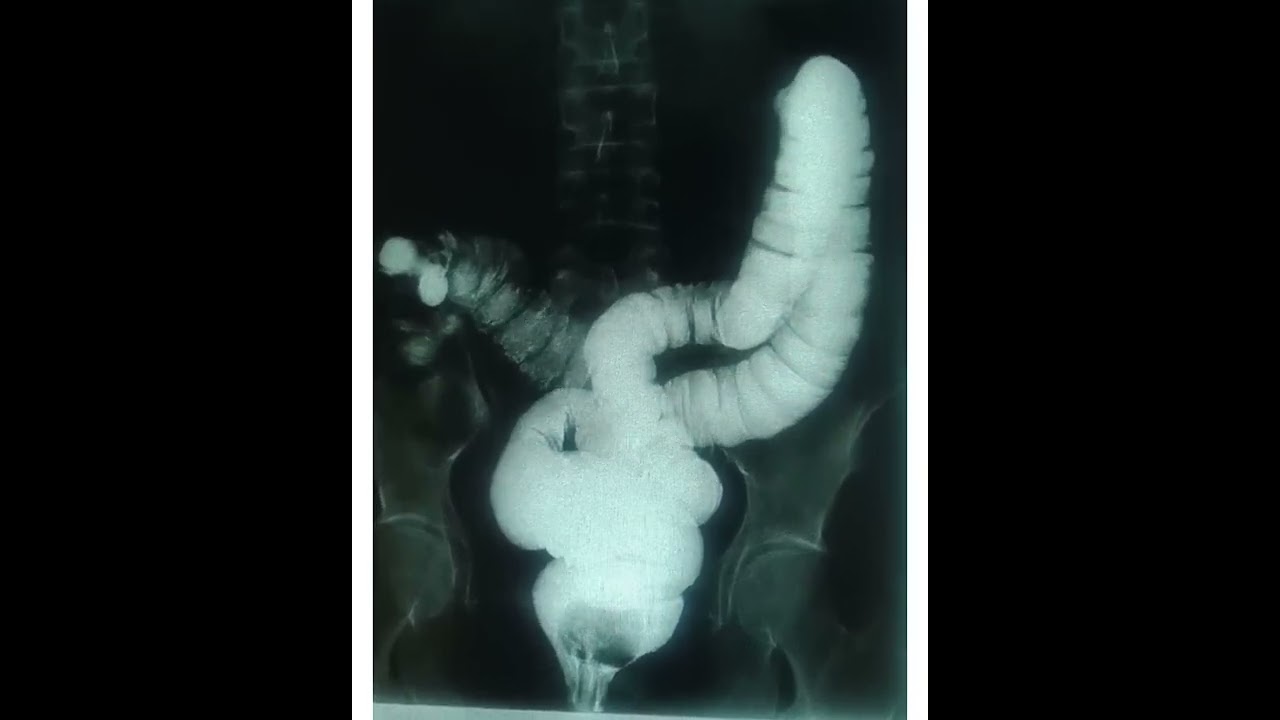

Sayangi Usus mu...

SHORTS

Triyoni Darpito A.Md.Rad

Gambaran Rontgen Colon/ Usus dengan sinar-X